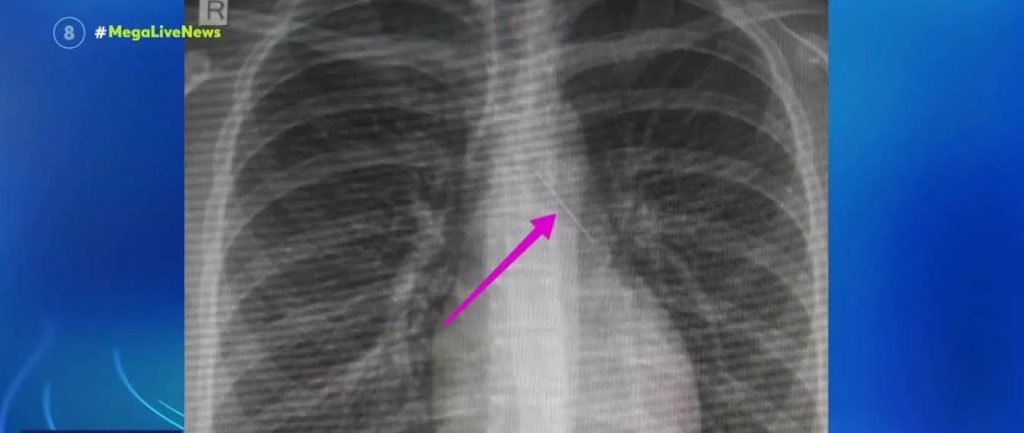

Οι εξετάσεις είχαν σταλεί στην Ελβετία καθώς εκεί υπάρχει εξειδικευμένο εργαστήριο για να εντοπιστεί η ύπαρξη ή μη συγκεκριμένων μεταβολικών και συνθετικών ναρκωτικών ουσιών που έχουν κυκλοφορήσει τους τελευταίους μήνες στην παράνομη αγορά και δεν μπορούν να αναγνωριστούν από το εργαστήριο του ΑΠΘ.

Το Ινστιτούτο έχει αναπτύξει μία συγκεκριμένη τεχνολογία και έχει παραλάβει ορισμένα μηχανήματα που μπορούν να προσδιορίζουν και να ανιχνεύουν συνθετικές ουσίες άγνωστης δομής, που έχουν πρωτοκυκλοφορήσει στην αγορά τους τελευταίους δύο με τρεις μήνες.